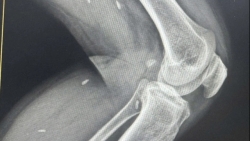

Khoa Chấn thương chỉnh hình - Phẫu thuật tạo hình, thẩm mỹ, Bệnh viện Đa khoa khu vực Bắc Quang (Tuyên Quang) vừa tiếp nhận một trường hợp tai nạn nghiêm trọng liên quan đến ...